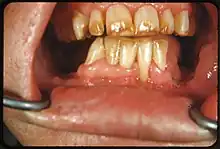

| Fluorose modérée | Toute la surface des dents est touchée, avec une usure marquée des surfaces en contact. Des taches brunes sont parfois présentes. |

| Fluorose grave | Toute la surface de toutes les dents est touchée ; avec piqûres discrètes éparses ou groupées. Présence de taches brunes. |